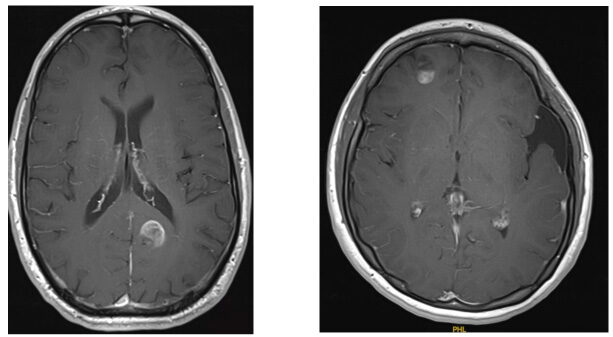

Different MRI sequences showing an extensive right frontal Grade 3 oligodendroglioma